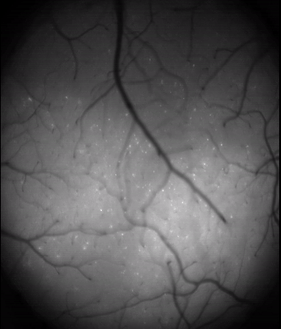

Visual scene reconstruction from brain activity

Designed and assembled a compact brain imaging Virtual Reality (VR) environment for mice. Collected and analyzed the brain activity during a VR navigation through natural scenes while tracking the animal’s pupil movements using Deeplabcut. Using deep encoder-decoder networks, reconstructed the images that the mouse was looking at from its neural activity in the visual cortex. Conceived and led the project during post-doc and was awarded a Simons Foundation grant. A paper containing our initial results is under review for NeuroIPS 2022.